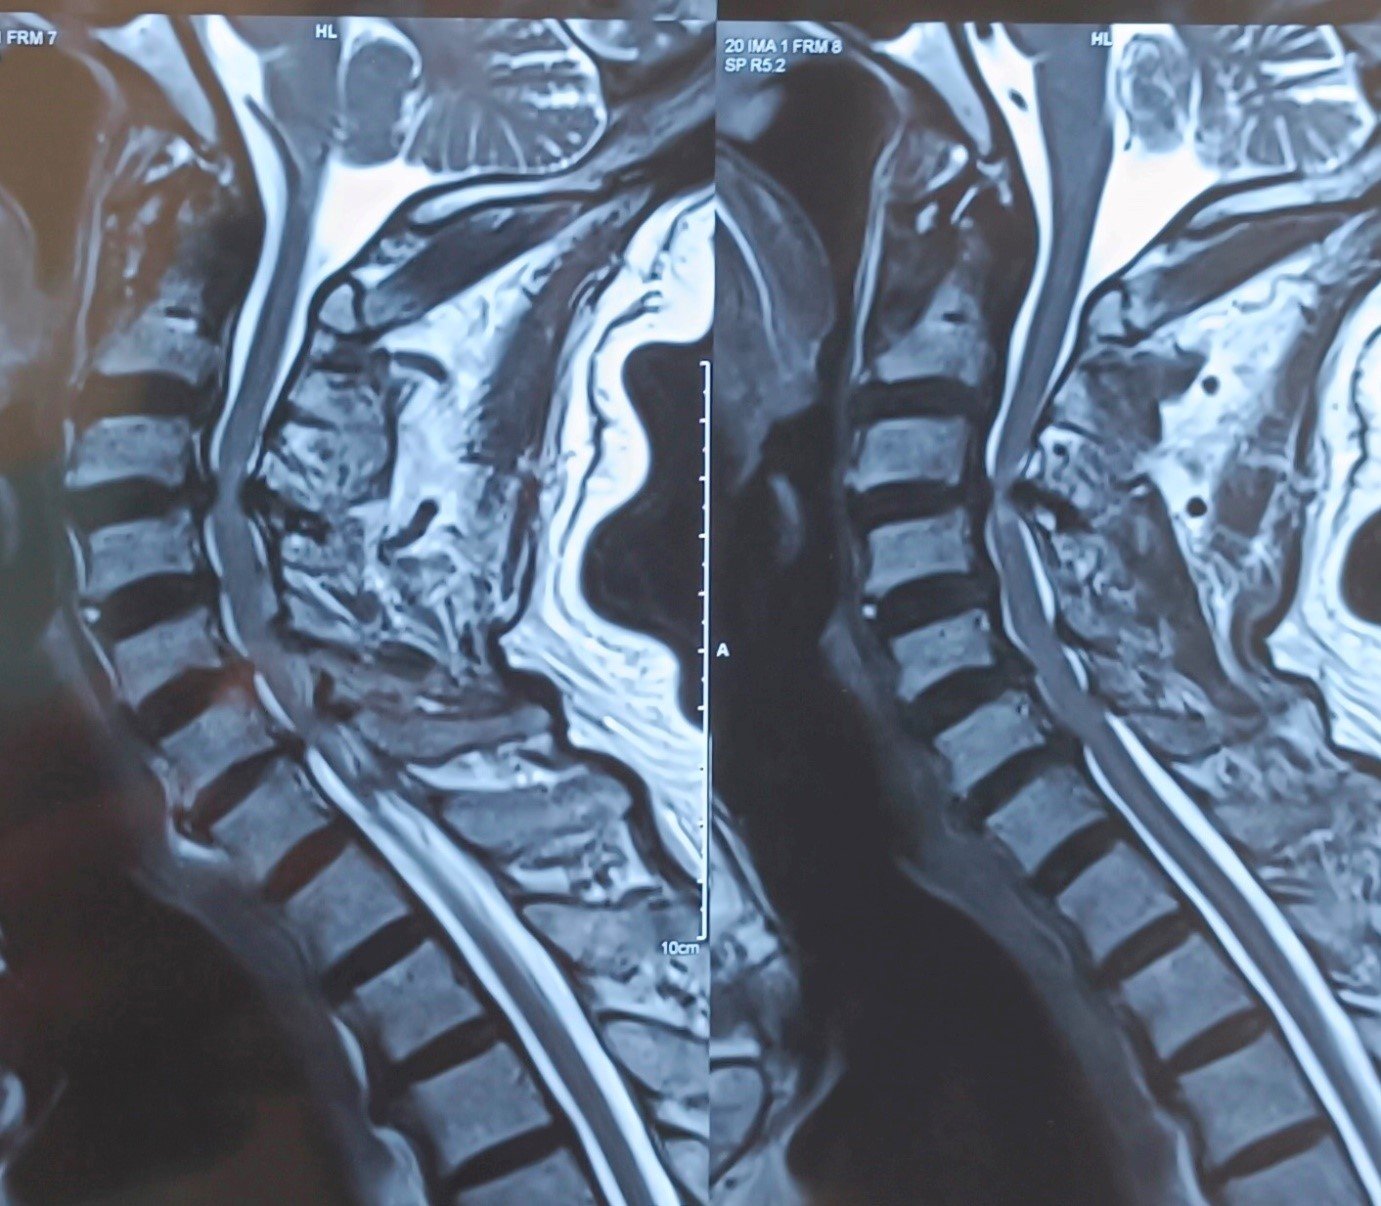

Cervical Myelopathy

Cervical Myelopathy Expert Care by Dr. Nitish Agrawal – Best Spine Surgeon in Pune Cervical Myelopathy is a serious spinal condition in which the spinal cord in the neck (cervical spine) becomes compressed. This compression is most commonly caused by degenerative changes in the spine, such as cervical disc prolapse,…